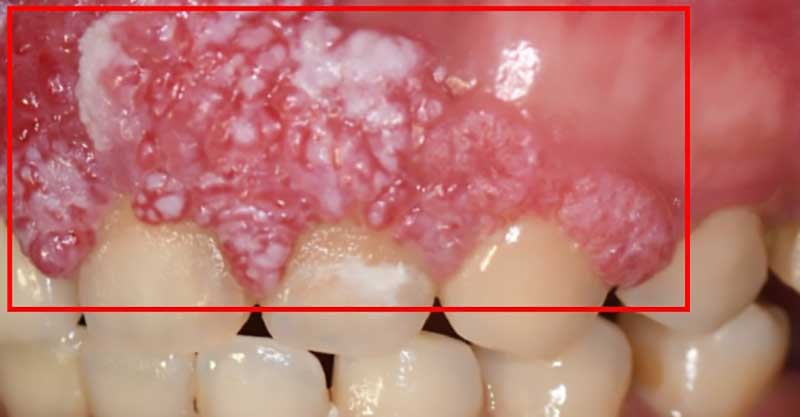

一位40歲的口腔癌患者許小姐,於2024年至中山醫學大學附設醫院口腔顎面外科就醫,該名患者罹患上顎牙齦癌,需手術切除大範圍上顎骨,不僅影響外觀,口內鄰近腫瘤的10顆牙齒亦需一併切除。術前運用電腦數位模擬技術,精準規劃腫瘤切除範圍及術後牙齒重建位置,並模擬將植體植入顴骨中,以彌補上顎骨缺損。手術當日,由中山附醫口腔顎面外科邱昱瑋主治醫師、陳怡孜主治醫師及陳珮吟主治醫師組成的醫療團隊主導,採用電腦數位模擬手術,先模擬腫瘤切除範圍,再模擬出切除後牙齒該有的排列位置,另外,關於上顎骨先前已被部分切除,透過電腦模擬將植體植入顴骨當中;手術當下,結合切割導版與電腦導航系統輔助,所有相關手術程序於同一日一次完成,精準完成上顎口腔癌腫瘤切除、頸部淋巴清除、顴骨植牙及游離皮瓣重建,大幅縮短治療時程,降低患者身體負擔,目前患者許小姐已成功恢復正常咀嚼功能,生活品質大幅提升。

中山附醫口腔顎面外科自2018年起,全面導入電腦數位模擬手術與精密導航技術,廣泛應用於顏面骨折外傷、正顎手術、腫瘤切除與重建等手術領域,透過術前精準模擬,不僅可減少手術傷口,也能提升顏面手術的安全性與準確度,協助患者重建外觀與功能,順利回歸正常生活。此外,中山附醫口腔顎面外科邱昱瑋主治醫師也提醒,即使不抽菸、不喝酒、不嚼檳榔,仍可能發生口腔癌,民眾若發現口腔內出現長期不癒的潰瘍、腫塊或異常疼痛,應儘早就醫檢查,把握黃金治療時機。